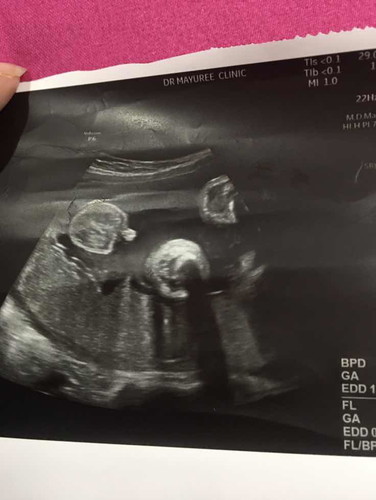

เมื่อวานไปหาหมอมาหมอบอกเอาไข่ลูกไปดูก่อนนะตัวแสบอยากจะออกแย่แล้วน้ำ2067 33+4wนัดผ่า14กรกฎาแต่เมื่อวานหมอบอกได้ว่าผ่าได้ตั้งแต่1กรกฎาคมเปนต้นไปตัวแสบอยากออกมาแย่แล้ว